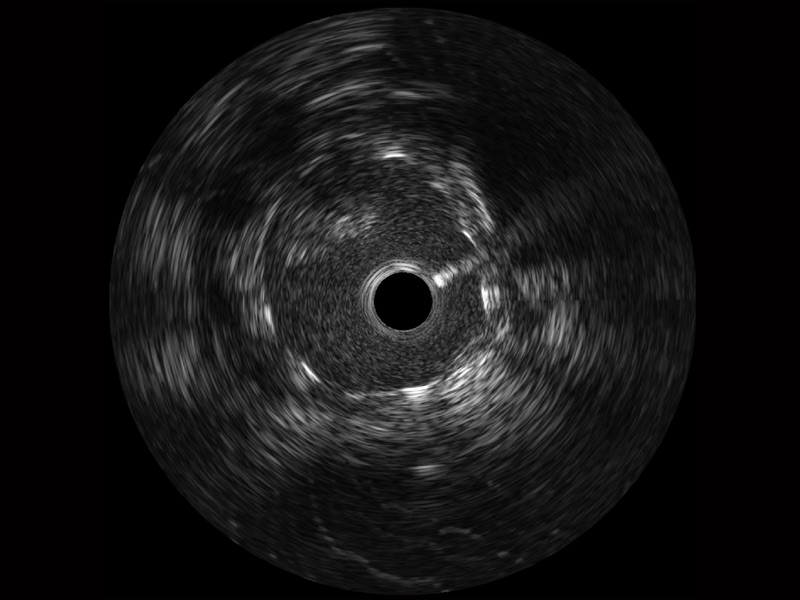

米兰官方网站宽频IVUS图像

传统IVUS图像

对比传统IVUS导管成像,米兰官方网站宽频IVUS图像的近场支架梁显影更细腻,远场中膜外血管仍清晰可辨,兼顾远中近,兼顾分辨力与穿透深度